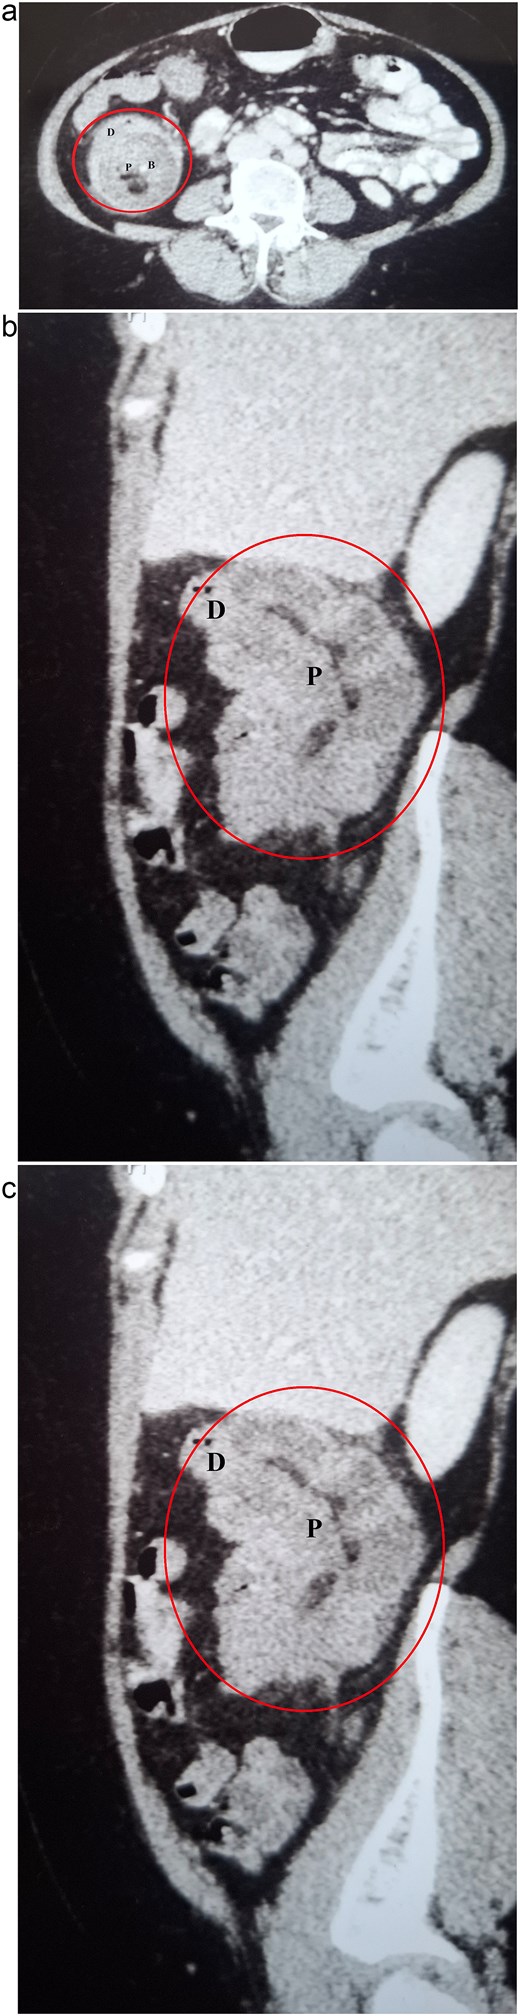

Her routine blood investigations were within normal limits. Ultrasound of the abdomen and pelvis showed distended bowel loops and a suspicious mass in the ascending colon. CECT scan of the abdomen was performed at 1 hour of presentation which revealed colocolic intussusception involving the ascending colon, along with dilated small bowel loops (Fig. 1). With the available clinical and radiological information, the patient was diagnosed with acute colocolic intussusception with features of subacute bowel obstruction. Following nasogastric tube decompression, she was started on intravenous fluids and prophylactic antibiotics were administered. Emergency laparoscopy, performed 3 hours after presentation, revealed a colocolic intussusception involving the ascending colon, with minimal dilated ileal loops. Minimal ascites was noted, with no visible lesions on the liver, or peritoneum, and no enlargement of mesenteric lymph nodes.

CECT abdomen demonstrating colocolic intussusception involving the ascending colon (encircled in red). (a) Axial view showing the characteristic multilayered appearance, with the proximal bowel (P) containing mesenteric blood vessels (B) and fat, surrounded by the thick-walled distal bowel (D). (b) Coronal view. (c) Sagittal view.